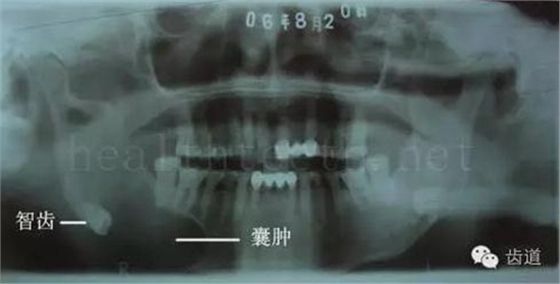

長期戴活動義齒不當或是戴不良修復(fù)義齒造成的口腔粘膜潰瘍,應(yīng)該引起高度警惕,因為這種潰瘍?nèi)菀装┳?/span> 黑毛舌 舌息肉,該患者同時伴有胃、食管息肉,后來看內(nèi)科了,具體情況不詳 四、孩子的牙齒問題 乳牙未退,牙根穿出牙齦對上唇粘膜造成刺激 乳牙滯留,也是孩子在退牙過程中最容易遇到的問題 五、牙齒發(fā)育上的問題 變色牙 氟斑牙 釉質(zhì)發(fā)育不全 四環(huán)素牙 牙神經(jīng)治療后的牙齒變色 10歲孩子剛剛萌出的牙齒變色 2、埋伏牙 左上乳3滯留,恒3未見萌出,曲面斷層片顯示牙齒埋伏 通過CT片確定埋伏牙齒具體的位置,顯示距離左側(cè)上頜竇很近,偏唇側(cè),這為手術(shù)定位提供了方便 手術(shù)中切斷、完整拔出,未損傷上頜竇 其他埋伏牙 3、多生牙 病例1 病例2 病例3,同時多生兩顆牙齒 4、各種畸形牙 畸形過小牙 融合牙:恒牙和乳牙都可以發(fā)生融合的情況(兩顆牙齒長在了一起) 畸形中央尖:在牙齒的中央,兩個牙尖之間又多長出一個牙尖,由于進食的磨耗很容易造成磨穿,神經(jīng)就會與外界相通,出現(xiàn)牙髓炎的癥狀 六、牙齒的外傷 牙冠折斷 牙根折斷 烤瓷牙打樁修復(fù)后牙根折斷 外傷后牙齒的全脫位,應(yīng)該保留牙齒盡早做再植手術(shù) 七、牙齒的慢性損傷 牙頸部楔狀缺損 牙冠劈裂及完整拔除后的情況 牙根縱裂及拔除后的情況 牙隱裂,牙齒表面有肉眼看不到的裂紋,細菌通過其進入牙髓,容易出現(xiàn)牙髓炎癥狀,嚴重可以造成牙齒的劈裂 這是一位來中國學(xué)習(xí)的俄羅斯大學(xué)生的牙齒,已經(jīng)做過了根管治療,牙齒咬合面有隱裂,通過鋼絲結(jié)扎固定,做鑄造金屬冠修復(fù)。 八、牙髓炎、根尖周炎 下面圖片都是慢性根尖周炎的病例,有了齲齒,進一步發(fā)展就是牙髓炎,如果此時沒有得到及時的治療,疾病會逐漸發(fā)展破壞到根尖的骨質(zhì),將骨質(zhì)破壞后就在牙齦上出現(xiàn)一個膿瘺,此時患者不再感覺到牙齒的疼痛了,往往忽視了治療,但是這種不痛并不是疾病好轉(zhuǎn)了,而是因為疾病的炎性滲出得到了引流,這個膿瘺會出現(xiàn)有時候變大了,有時候又變小了,但是如果不治療是不會自己愈合的,只有經(jīng)過完善的根管治療后才有好轉(zhuǎn)的可能,但是在疾病的治療中時間是起決定作用的,時間拖得越晚,好轉(zhuǎn)的可能性越小,經(jīng)過根管治療后如果膿瘺還是沒有消失,就需要做根尖刮治術(shù),如果仍然沒有好轉(zhuǎn),就只能做根尖切除術(shù)了,這對牙齒的穩(wěn)固是不利的。下面圖片中在膿瘺中插入了一個牙膠尖,是我們做根管充填用的材料,是非常軟的,就是在口腔牙齦瘺管的地方插進去,通過拍牙片可以清晰地看到它到達的位置,從而確定發(fā)病的牙齒,此處是為了讓大家看得更清楚。 門牙兩個膿瘺 烤瓷牙修復(fù)后牙齦出現(xiàn)兩個膿瘺,插入牙膠尖,牙片顯示牙膠尖到達的位置就是根尖炎癥的位置,根尖骨質(zhì)密度降低(發(fā)黑的地方) 牙齒根尖膿瘺,治療前、中、后的圖片對照,完善根管治療后膿瘺明顯消失了 牙髓炎和根尖炎治療的關(guān)鍵就是根管治療 合格的根管充填治療 不良的根管充填治療 九、關(guān)于智齒(第八顆牙) 四顆長不出來的智齒 智齒反復(fù)發(fā)炎造成的頰瘺,膿腫切開引流后面部會留疤 智齒造成的頜骨囊腫,手術(shù)切除后需要植骨 十、各種錯合畸形 開合 深覆合 深覆蓋,上頜前突 反合(地包天) 牙齒排列擁擠 來源:牙醫(yī)愛看的 KQ88口腔醫(yī)學(xué)網(wǎng)